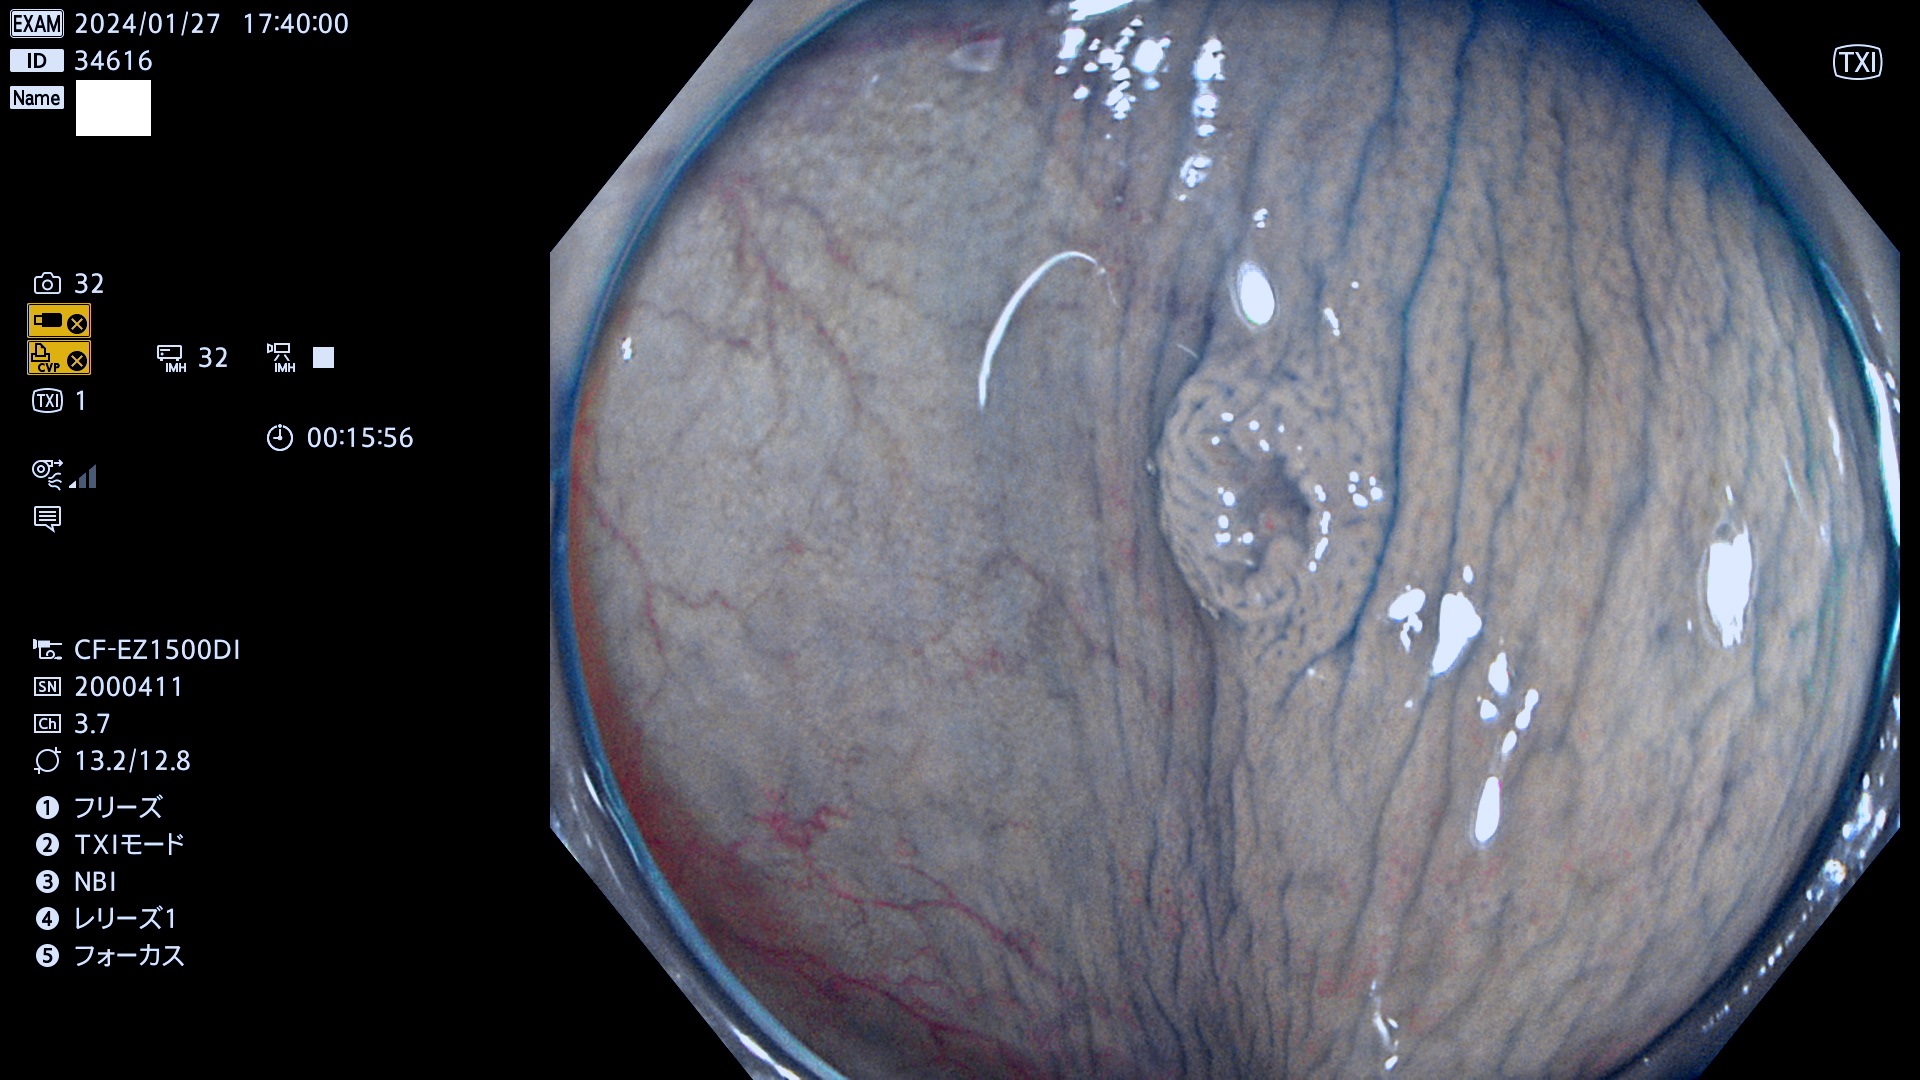

表面型腺腫(Flat Adenoma)の中で、完全に平坦な物をUb、陥凹している物をUcと呼びます。平坦隆起型(Ua)よりも、発見が難しく危険な病変です。

専門的)Uc=De Novo癌? 内視鏡の解像度が低かった時代、このような説もありました。しかし今日の高精度内視鏡では良性の微小なUc型腺腫が日常的に見つかります。私見ですが「Ucこそが多段階発癌(Adenoma-Carcinoma Sequence)のMain Route」と考えます。

毎週の検査(木・金・土・日)に発見されたUb、Uc型・腺腫を、その週の日曜の夜にUPし1週間、提示します。

抽出の対象期間 2024年1月25日(木)〜1月28(日)の4日間(40件の検査)9件